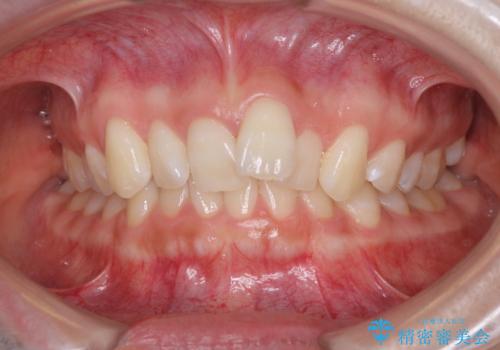

[ 総合歯科診療 ] がたつきの改善とセラミック治療

![[ 総合歯科診療 ] がたつきの改善とセラミック治療の症例 治療前](https://seimitsushinbi.jp/wp/wp-content/uploads/2024/03/f0f438a14c56b185411649f48b5b188c-500x350.jpg?v=1710833163)

![[ 総合歯科診療 ] がたつきの改善とセラミック治療の症例 治療後](https://seimitsushinbi.jp/wp/wp-content/uploads/2024/03/7212917eb9c4ef33050c52e7f9724490-500x350.jpg?v=1710833188)